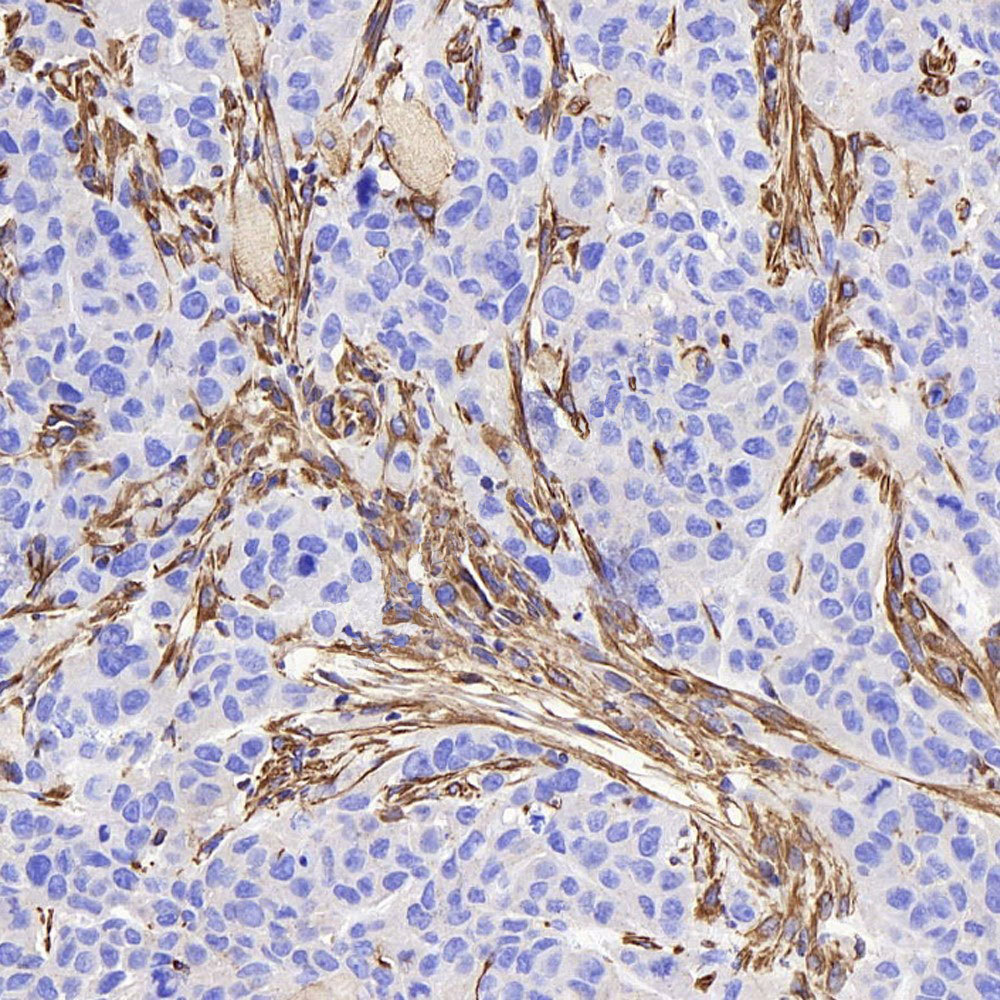

免疫組化,是應用免疫學基本原理——抗原抗體反應,即抗原與抗體特異性結合的原理,通過化學反應使標記抗體的顯色劑(熒光素、酶、金屬離子、同位素)顯色來確定組織細胞內抗原(多肽和蛋白質),對其進行定位、定性及定量的研究,稱為免疫組織化學技術(immunohistochemistry)或免疫細胞化學技術(immunocytochemistry)。

實驗結果展示:

切片脫蠟至水-抗原修復-3%的雙氧水處理-畫圈-血清封閉-一抗4℃過夜孵育-二抗室溫孵育-顯色-蘇木素染核-脫水、透明、封片-鏡檢